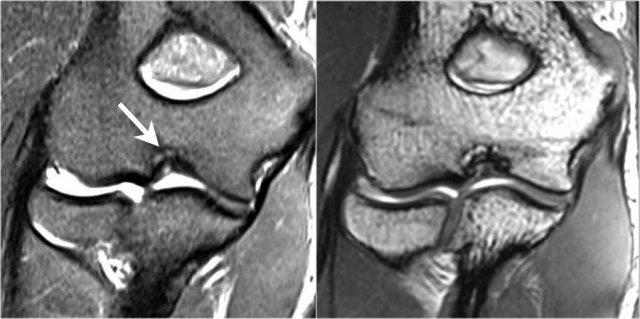

OC lesion of trochlea

Những hình ảnh này của một bệnh nhân bị đau khuỷu tay phía trước.

Không có chấn thương gần đây.

Chẩn đoán lâm sàng là viêm gân cơ nhị đầu hoặc viêm túi hoạt dịch vùng nhị đầu.

Các phát hiện trên hình ảnh MRI mặt phẳng vành khá bất thường.

Nếu bạn thấy điều này ở chỏm con, bạn sẽ gọi đó là tổn thương sụn xương chỏm con.

Đây được gọi là tổn thương sụn xương của ròng rọc.

Lưu ý các thay đổi dạng nang nhỏ (mũi tên trắng).

There is also a small cartilage defect.

Tổn thương xương sụn của ròng rọc thường gặp ở bệnh nhân trẻ tuổi, có bộ xương chưa trưởng thành.

Tổn thương xuất hiện ở ròng rọc bên như trong trường hợp này do tình trạng duỗi quá mức lặp đi lặp lại trong vùng có nguồn cung cấp máu kém.

Nó cũng được thấy ở ròng rọc trong do lỏng lẻo và va chạm sau trong.

Đây là một bệnh nhân khác.

Lưu ý rằng đây là bệnh nhân trẻ tuổi, vì sụn tăng trưởng vẫn còn mở.

Có một tổn thương xương sụn lớn ở ròng rọc xương đùi bên ngoài (mũi tên vàng).

Lưu ý phù nề ở xương dưới sụn (mũi tên đỏ).

Sụn khớp vẫn còn nguyên vẹn.